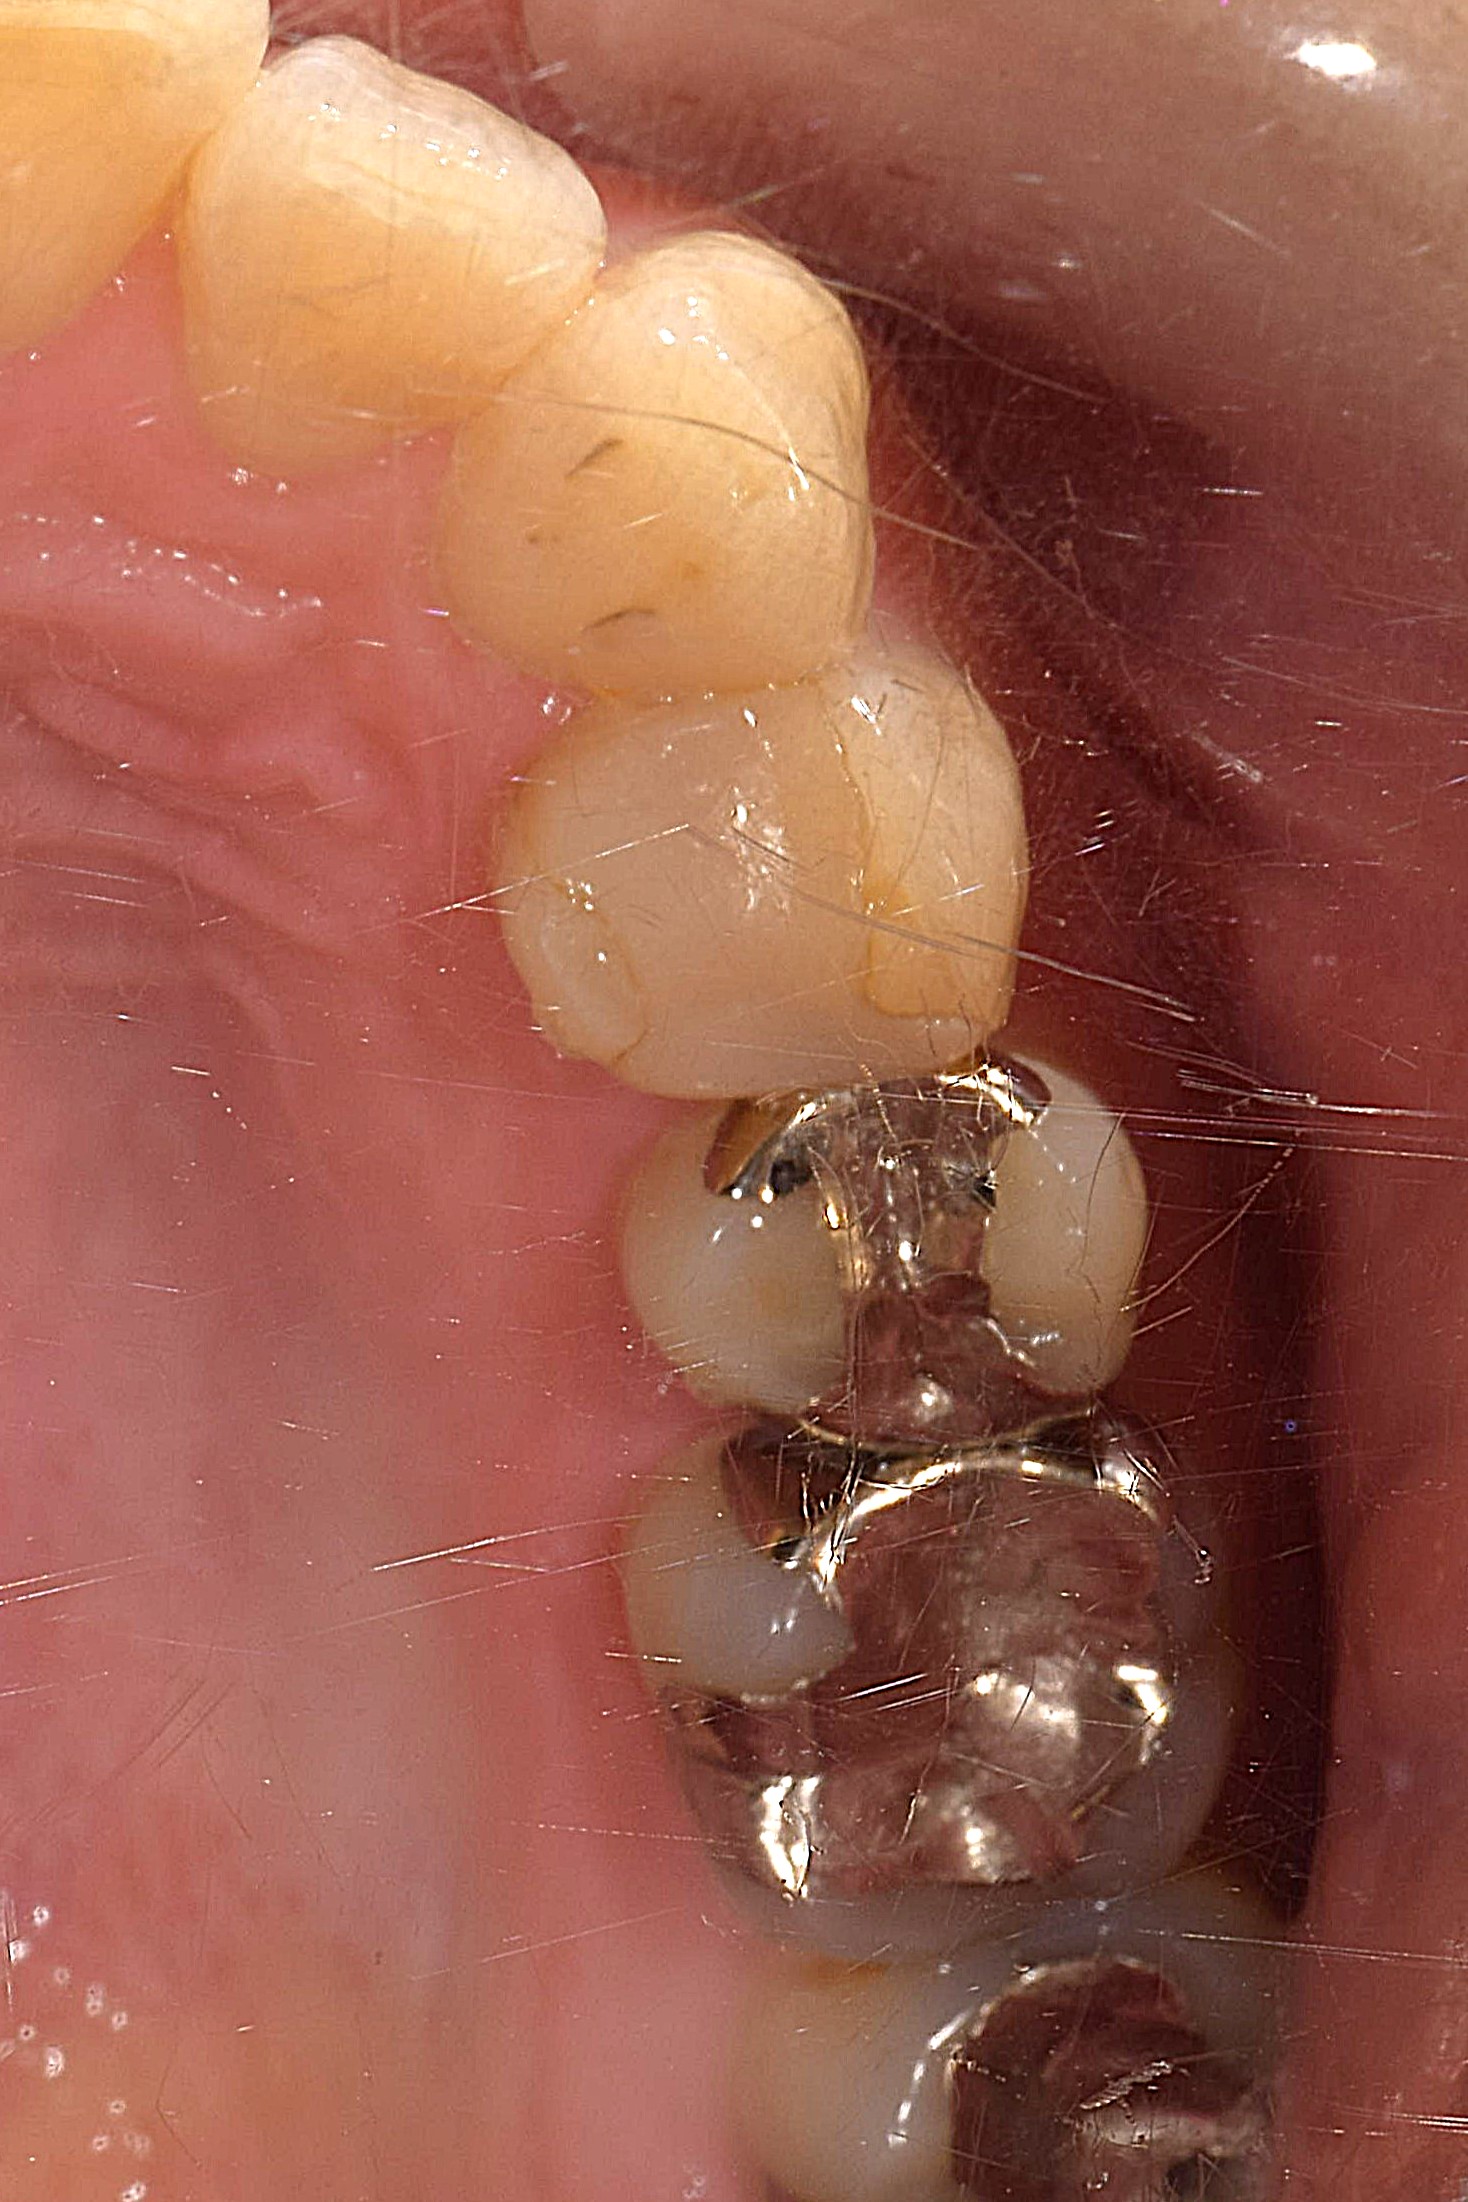

| 原因 | 銀歯(インレー)やプラスティック(レジン充填)の隙間から虫歯菌が侵入し再発 |

| 治療法 | 虫歯の部分を取り除き、光学スキャンして CEREC Inray&Onlayにて歯冠修復 |